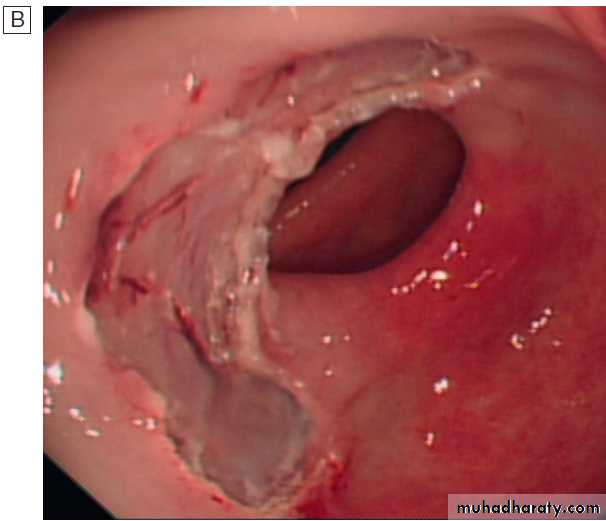

stratification in acute upper GI bleedingMajor stigmata of recent haemorrhage and endoscopic treatment. A Active arterial spurting from a gastric ulcer. An endoscopic

C Haemostasis is achieved after endoscopic clipping of the bleeding vessel in the duodenum.